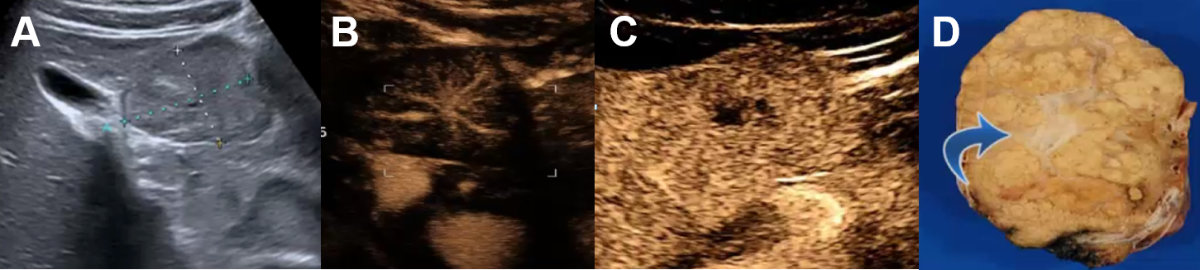

Focal nodular hyperplasia is the second-most common benign hepatic tumour with a prevalence of 0.03% (0.4 to 3% in autopsy series) in predominantly middle-aged (35 to 50 years) female patients (10:1 female ratio) with mostly solitary manifestations smaller than 5 cm (multiple focal nodular hyperplasia in 20–30% of cases) [1]. In most cases, the focal nodular hyperplasia size remains stable over time [48]. On a conventional ultrasound, focal nodular hyperplasia usually appears slightly hypo- or isoechoic (figure 15A), sometimes with a lobulated contour and a pseudocapsule, which is caused by compression of the surrounding liver tissue or vessels and sometimes with a central scar (figure 15C). Central feeding arteries can be demonstrated on colour Doppler with spoke-wheel pattern (figure 15B) with typical arterial flow in the pw-Doppler. However, malignant tumours can also present the spoke-wheel sign, for instance. in fibrolamellar hepatocellular carcinoma [17, 49]. Therefore, contrast-enhanced imaging is mandatory in suspected focal nodular hyperplasia.

Figure 15Focal nodular hyperplasia on conventional ultrasound and CEUS. A Symptomatic focal nodular hyperplasia on ultrasound next to the gallbladder. B CEUS with centrifugal arterial contrast enhancement (“spoke wheel sign”). C Late phase with central scar (hypoenhancing) of the dystrophic central artery (D, blue arrow) shown on the resection sample.

CEUS is an excellent imaging modality to accurately diagnose focal nodular hyperplasia, particularly if the diameter is below 3 cm [1]. The typical finding shows a fast arterial centrifugal uptake of the contrast agent, which becomes hyperechoic in seconds. This fast, dynamic process can be missed by CT or MRI. Hyperenhancing focal liver lesions can be demonstrated in the arterial, portal-venous phase up to the late venous phase (sometime iso-enhancing in the late venous phase), but in most cases without washout (figure 15C) [3, 17]. This vascular malformation can be divided into different groups by CEUS according to the vascular patterns. Atypical variants of focal nodular hyperplasia, that is, without a central scar and/or with decentral contrast enhancement, are reported in about 20% of cases [48, 50]. In general, CEUS is more accurate than MRI in focal nodular hyperplasia smaller than 3 cm, whereas the opposite is true in larger focal nodular hyperplasia lesions [1].